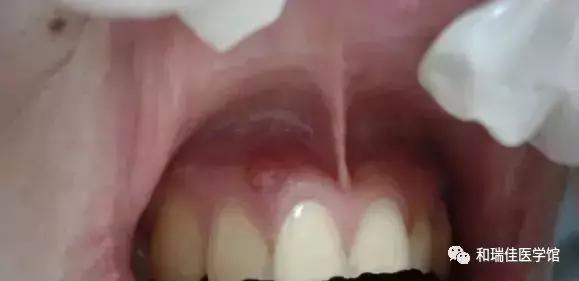

只是个小包包吗?其实并没那么简单!你看到的只是表面现象,长脓包说明牙龈内的牙根已经发炎,细菌感染牙髓演变成牙根炎症,引起牙槽骨蔓延,牙槽骨遭到炎症影响,所以牙龈上才会鼓起一个脓包,从根尖到牙根的瘘管,脓包内产生的分泌物由此流出。而出现这种问题就必须去看牙医了,否则情况就会越来越严重。

当蛀牙蛀到牙髓的时候,细菌感染了牙髓后逐渐繁殖,炎症通过牙髓进而发展大牙根、牙槽骨然后再开始慢慢蔓延,牙槽骨遭到破坏,吸收,便会在牙龈上鼓起一个脓包,形成从根尖到牙根的瘘管,炎症产生的分泌物便由此流出。